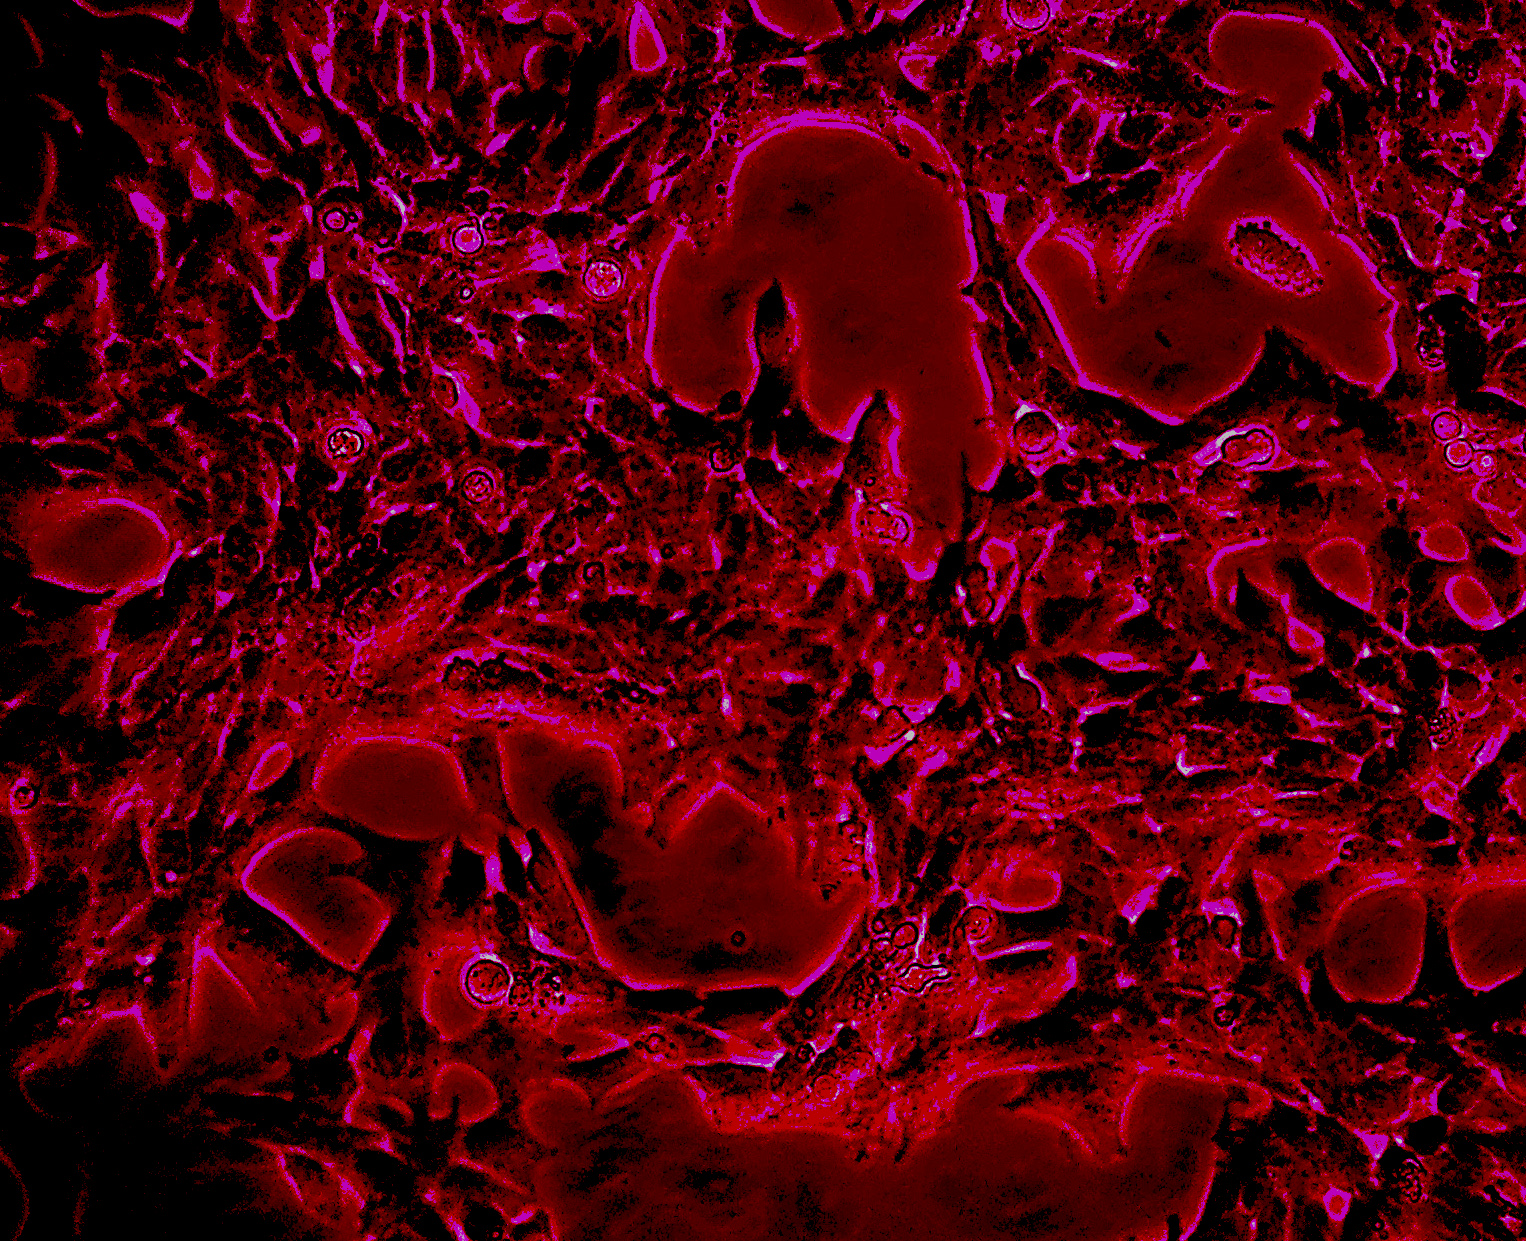

Forschende des Inselspitals, der Universität Bern sowie der Universität Barcelona haben entdeckt, wie die Produktion von spezifischen menschlichen Sexualhormonen, sogenannten Androgenen, unterbrochen wird. Die Erkenntnisse können dazu beitragen, neue Therapieansätze zu entwickeln, da eine Überproduktion dieser Androgene zu Krankheiten wie Prostatakrebs oder dem polyzystischen Eierstocksyndrom führen kann.

Nun hat eine Gruppe um Amit Pandey von der Universitätsklinik für Kinderheilkunde des Inselspitals Bern und dem Department for BioMedical Research (DBMR) der Universität Bern eine Gen-Mutation entdeckt, die dafür verantwortlich ist, dass dasjenige spezifische Enzym, das die Produktion von Androgenen steuert, geschädigt ist. Die Ergebnisse der Studie, die im Open Acess-Journal Pharmaceuticals publiziert wurden, könnten dazu führen, einen effizienteren Therapieansatz für kastrationsresitstenten Prostatakrebs zu entwickeln.

Weitere Analysen in Bern ergaben, dass im mutierten Gen die Sexualhormone nicht mehr an dessen Zentrum andocken können. Wie die Berner Forschenden auch zeigen konnten, resultiert aus dem mutierten Gen ein geschädigtes Protein, das für die Produktion des Androgens-Vorläufers zuständig wäre. Entsprechend fehlten beim untersuchten Patienten Androgene. «Wir hoffen, dass dank diesen Erkenntnissen Prostatakrebs und auch das polyzystische Eierstocksyndrom bei Frauen besser behandelt werden können», sagt Pandey.